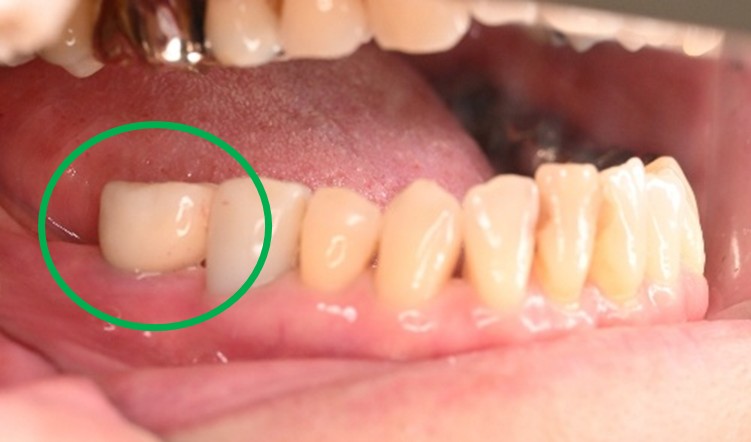

男性 Yさん 60代 (インプラント)

主訴

右下の奥歯の歯肉が痛い。時々血が出たり、腫れたりする。

治療内容

右下のブリッジの支台になっている前方の歯が、歯根破折を起こしていましたので抜歯しました。インプラントを右下第一、第二大臼歯部に2本埋入しました。

所感

実はこの患者さんは、2014年に右下の第二大臼歯(一番奥の歯から2番目の歯)を歯根破折により抜歯し、その際の治療法としてブリッジを選択されました。そして今回、ブリッジを支えていた歯(第一大臼歯)がついに歯根破折を起こしてしまいました。

ブリッジは、3本分の歯を2本の歯で支えるため、支える歯の負担が大きくなり、歯根破折を起こす危険性が高くなります。

今回の抜歯後は、歯が2本ない状態になるので、そこを補う方法についてご説明しました。選択肢は再度ブリッジを入れるか、インプラントになります。ブリッジにして支える歯がまた折れてしまうと歯が3本ない状態になる可能性があるため、インプラントを選択されました。もし11年前にブリッジではなくインプラントを選んでおられたら、今回の歯根破折や抜歯は起きなかったかもしれません。ブリッジは、噛む力の強い方、歯ぎしりをする方、硬い食べ物が好きな方は、支えの歯の負担がより大きくなるのでおすすめできません。

インプラントは、それ自身が単独で植立しているので、他の歯に負担がかかりません。インプラントは、欠損を補う最良の方法と考えます。

インプラント2本:¥726,000(税込)

Before

抜いた歯 真二つにわれています

After